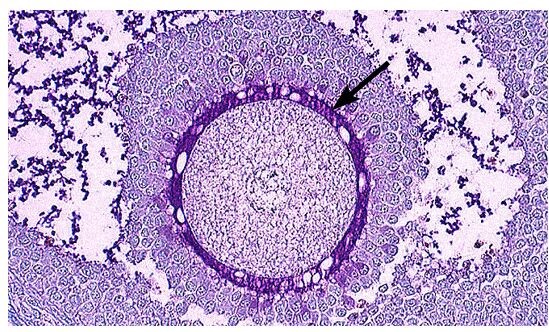

A child is brought to the pediatrician because of perianal itching, which has been disturbing the child's sleep. Physical examination reveals scaly skin in the perianal region. The physician instructs the parents to place transparent tape on the perianal region the next morning, and then retur n to the office. In the office, the tape is transferred to a microscope slide, and low-power examination of the tape reveals oval eggs that are flattened along one side. The microorganism most likely responsible for the child's symptoms is